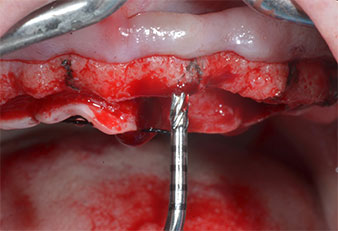

Uno strumento piezoelettrico (Piezomed I1) a forma di fiamma, rivestito in diamante, è stato usato per contrassegnare le posizioni dell'impianto e per eseguire una preparazione pilota (Fig. 3). Si è prestato attenzione a utilizzare un movimento verticale ascendente e discendente, con potenza ridotta, irrigazione completa e bassa pressione (inferiore a 300 g). Successivamente è stato applicato uno strumento pilota (Piezomed I2A/I2P) per l'ingrandimento iniziale delle sedi dell'impianto del diametro di 2 mm (Fig. 4), seguito da un inserto da 3 mm (Fig. 5).